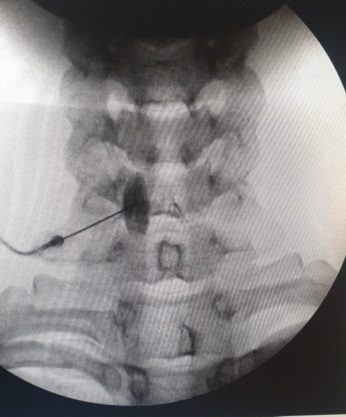

Με τον ασθενή σε πρηνή θέση και υπό τοπική αναισθησία, εισάγεται κάτω από ακτινοσκοπική καθοδήγηση μια βελόνα που διέρχεται από το πλάγιο τμήμα του πρώτου οσφυϊκού σπονδύλου, το άκρο της οποίας στην τελική του θέση φθάνει στην περιοχή ακριβώς μπροστά από την αορτή. Γίνεται έγχυση σκιαγραφικού για απεικόνιση του πλέγματος και αμέσως μετά δίνεται το τοπικό αναισθητικό και η κορτιζόνη. Μέσω της διαδικασίας αυτής μπορούν να εγχυθούν και νευρολυτικοί παράγοντες, όπως η αλκοόλη και η φαινόλη, οι οποίοι έχουν καταστροφική δράση. Το block με τοπικό αναισθητικό και κορτιζόνη έχει δράση για λίγες μέρες. Όσοι ασθενείς ανταποκριθούν θετικά, μπορούν να υποβληθούν σε δεύτερο χρόνο σε νευρόλυση με χρήση ραδιοσυχνοτήτων, η οποία προσφέρει μακρά θεραπευτική δράση.